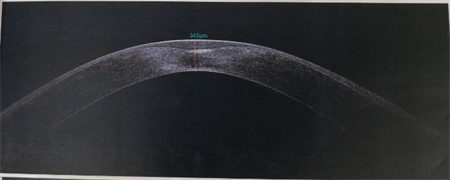

商旭敏副主任告訴我們,小蕓的右眼已經(jīng)是圓錐角膜后期,角膜厚度僅有343,再繼續發(fā)展下去,就會(huì )水腫破裂。由于圓錐角膜都是雙眼發(fā)病,小蕓的左眼此時(shí)也開(kāi)始出現圓錐角膜的癥狀了。

▲小蕓右眼厚度343,左眼厚度523